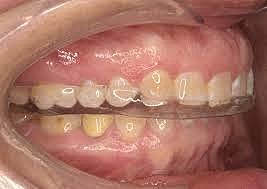

• Toma de modelos para guarda oclusal

Toma de modelos para guarda oclusal

Con la finalidad de proteger las restauraciones directas se confeccionará una guarda oclusal desprogramadora. Se tomarán modelos de estudio y se bajará con un acetato según el grosor adecuado para el paciente.

• Entrega de guarda oclusal

Entrega de guarda oclusal

Después de retirar el acetato del modelo y de haberlo pulido se hace entrega del mismo al paciente con las indicaciones pertinentes.